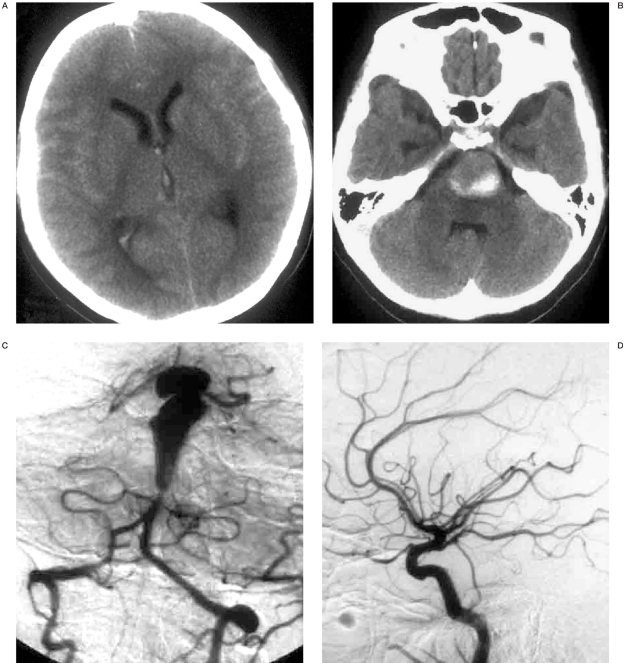

This 31-year-old woman experienced sudden violent headache, vomiting and loss of consciousness rapidly with aconuresis. Computed tomography (CT) revealed massive subarachnoid hemorrhage (SAH), slight right lateral and third intraventricle hemorrhage, and left pons was compressed by a high density mass with a diameter of 2 cm (figures 1A,B). The patient regained consciousness in 20 days. After waking up, the patient presented with dysarthria, tetraparesis, and forced laughing and crying. The patient was transferred to our institute when she was stable. Neurologic examination showed frequent laughter and crying outbursts, bilateral spasticity and weakness of limbs, bilateral ankle clonus, and right positive Babinski sign. Because of a metal implantation in her left leg prior to the onset, she could only be re-examined by CT. SAH had been absorbed; mass effect was the same as the previous one, and edema inside the pons could be seen (figure 1B).

Figure 1.

A 31-year-old woman with sudden-onset of headache, vomiting and loss of consciousness. CT revealed SAH (A) and a high density mass with a diameter of 2 cm compressing the left pons (B). Cerebral angiography showed that a huge dissection distal to the AICA (C), and bilateral PCoA were prominent (D,E). After making a basket with 3D coils (F), vertebral angiogram showed occlusion of the dissection and proximal aneurysm with patency of the bilateral AICA (G). But the upper part of the aneurysm could still be stained by bilateral PCoAs (H,I). Follow-up seven months after embolization confirmed the complete occlusion of the dissection (J), and thrombosis and vanishing of distal part of BA that had been fed by bilateral PCoAs (K,L).

Cerebral angiography was performed and a huge dissecting aneurysm distal to the bilateral anterior inferior cerebellar arteries (AICA) was noted (figure 1C). The bilateral posterior cerebral arteries (PCA) and superior cerebellar arteries (SCA) were involved in the aneurysm. Contrast medium was stagnant in the upper part of the aneurysm. Bilateral posterior communicating arteries (PCoA) were prominent (figures 1D,E).

The procedure was performed under general anesthesia after informed consent was obtained two days after the angiogram. A 5F-guiding catheter was introduced into the left cervical vertebral artery under full heparinization. Then a microcatheter was navigated into the proximal part of the dissecting aneurysm. Two large 3D coils were adjusted carefully to make a basket inside the aneurysm (figure 1F). Then more coils were detached in the dissection. Finally, the last coil was deployed extending from aneurysm to the adjacent normal BA segment just above the bilateral AICA. Vertebral angiogram showed occlusion of the DA with patency of the bilateral AICA (figure 1G). Unfortunately, the bilateral carotid artery angiogram revealed that upper part of the aneurysm could still be stained by bilateral PCoAs and the contrast medium remained stagnantly (Figures 1H,I).

The patient was followed up for seven months after embolization. She could speak stammeringly and walk slowly by herself. Cerebral angiograms confirmed the complete occlusion of the total dissection (figure 1J). Left and right carotid angiogram showed thrombosis and vanishing of the distal part of the dissection that had been fed by bilateral PCoAs (figures 1K,L).